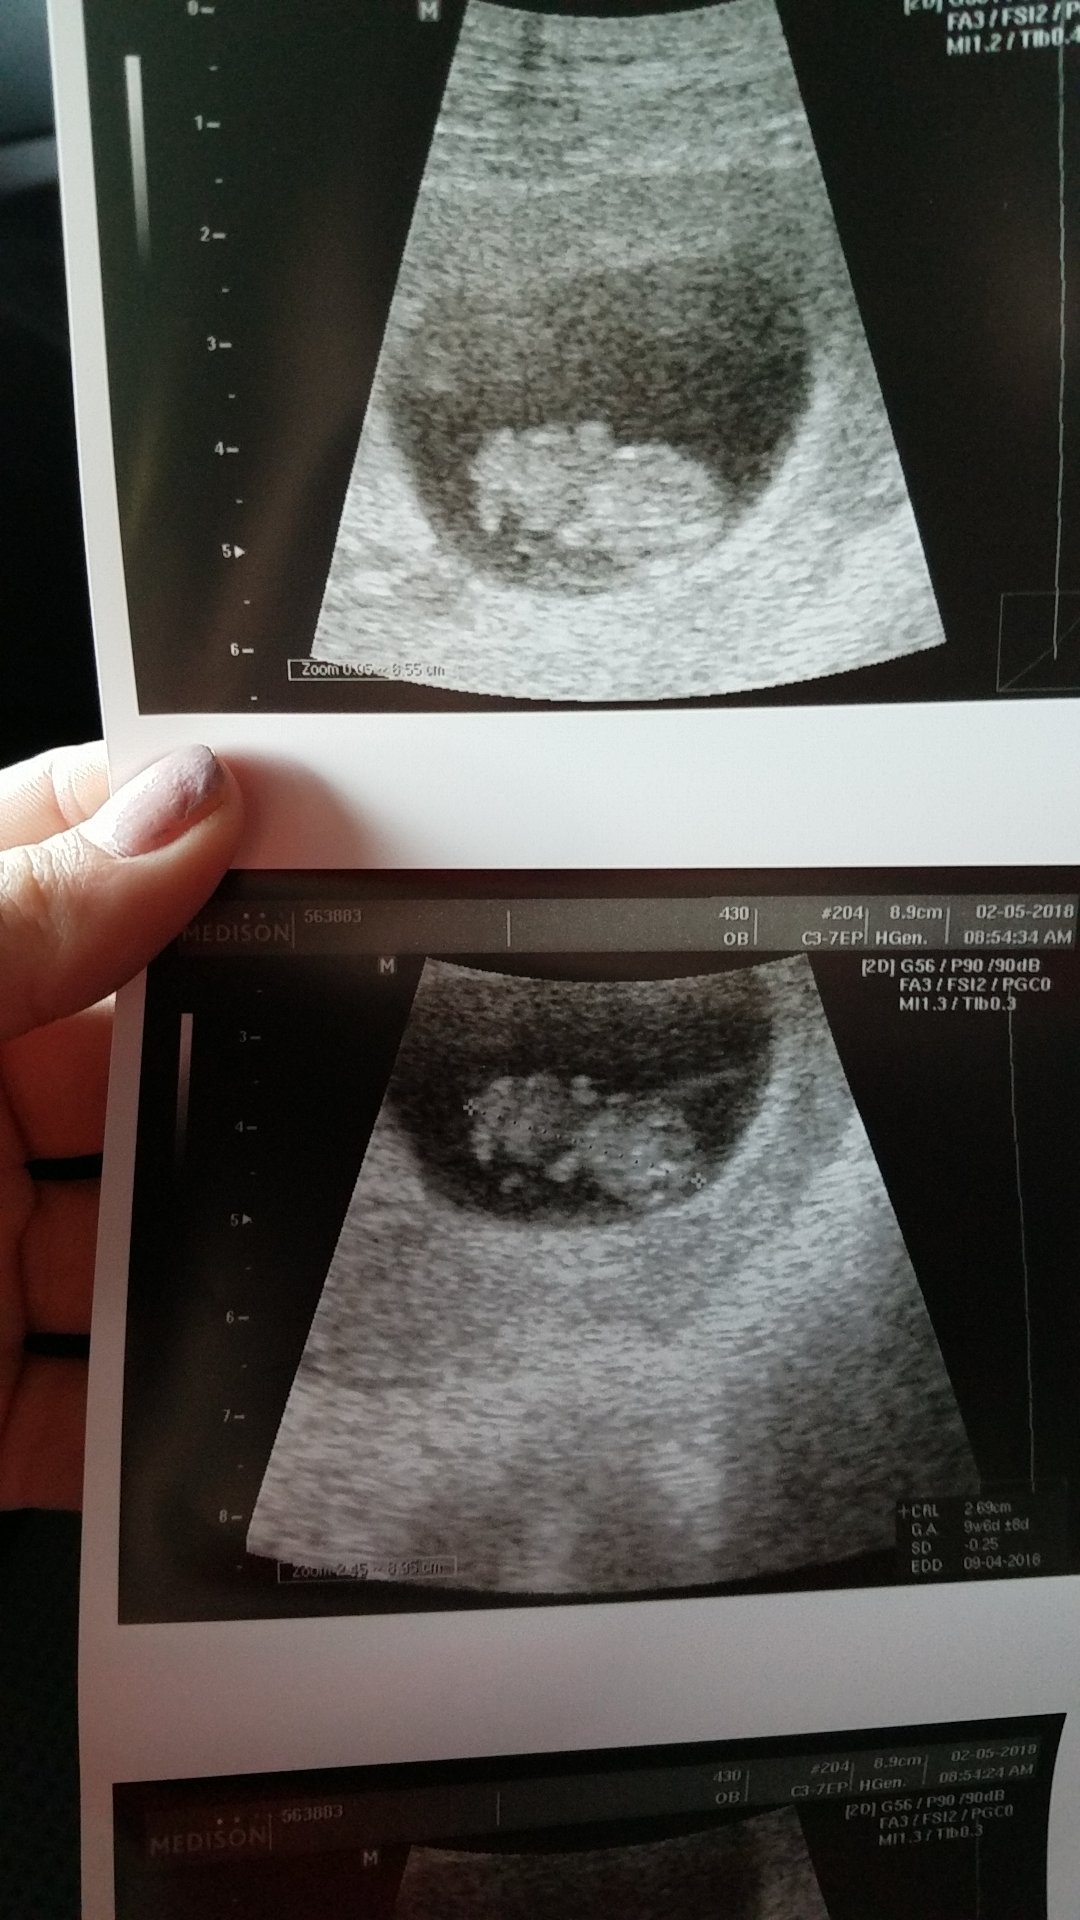

• Here is our little bean... Measuring 7 weeks (LMD is 7+3) but doc is keep DD at 9/30